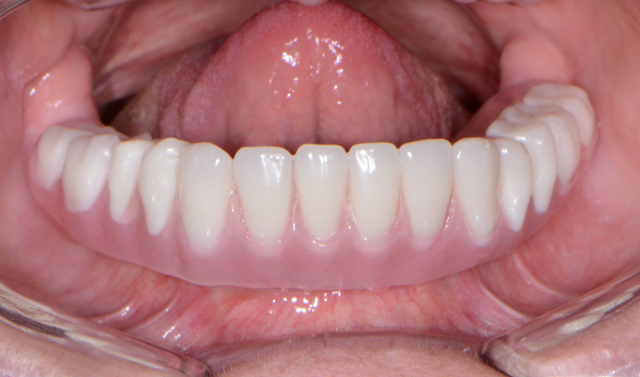

Approximately three to four months later (Fig. 12), the healing caps were removed from the Engage (OCO Biomedical) dental implants in the mandibular ridge and LOCATOR R-Tx (Zest Anchors) overdenture attachments placed (Fig. 13) and tightened to 30 Ncm. Free-standing attachments like the LOCATOR R-Tx used to retain overdentures provide numerous advantages, including enhanced esthetics and phonetics as well as ease of maintenance and simplified hygiene.

Fig. 13 Fig. 14

The first step was to brush a thin coat of adhesive into the overdenture recesses (Fig. 14) to enhance retention between the denture base and the hard reline material. Petroleum jelly was applied to the surrounding surfaces of the denture to prevent unwanted adherence of excess material. Once mixed, the Rebase II material (Figs. 15 & 16) was placed into a plastic dispensing syringe and injected up to two-thirds the height of each recess as well as on to the attachments. During seating, the prosthesis was gently held in place by hand. After a total of about three minutes, the overdenture with the incorporated retention caps was removed. Any excess material was removed with a trimming bur (Fig. 17). At the completion of the prosthetic phase, the patient stated how pleased she was to be able to smile and function without the prosthesis wobbling or falling out (Fig. 18). Most importantly from a clinical standpoint, we were pleased to see the areas in the upper and lower arches healthy and infection-free.

Fig. 17 Fig. 18